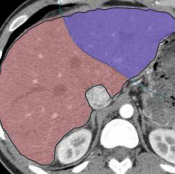

Virtual liver resection and volumetric analysis of the future liver remnant using open source image processing software (2010)

van der Vorst, Joost R and van Dam, Ronald M and van Stiphout, Rogier SA and van den Broek, Maartje A and Hollander, Ilona H and Kessels, Alfons GH and Dejong, Cornelis HC

World journal of surgery, vol. 34 (10): 2426–2433